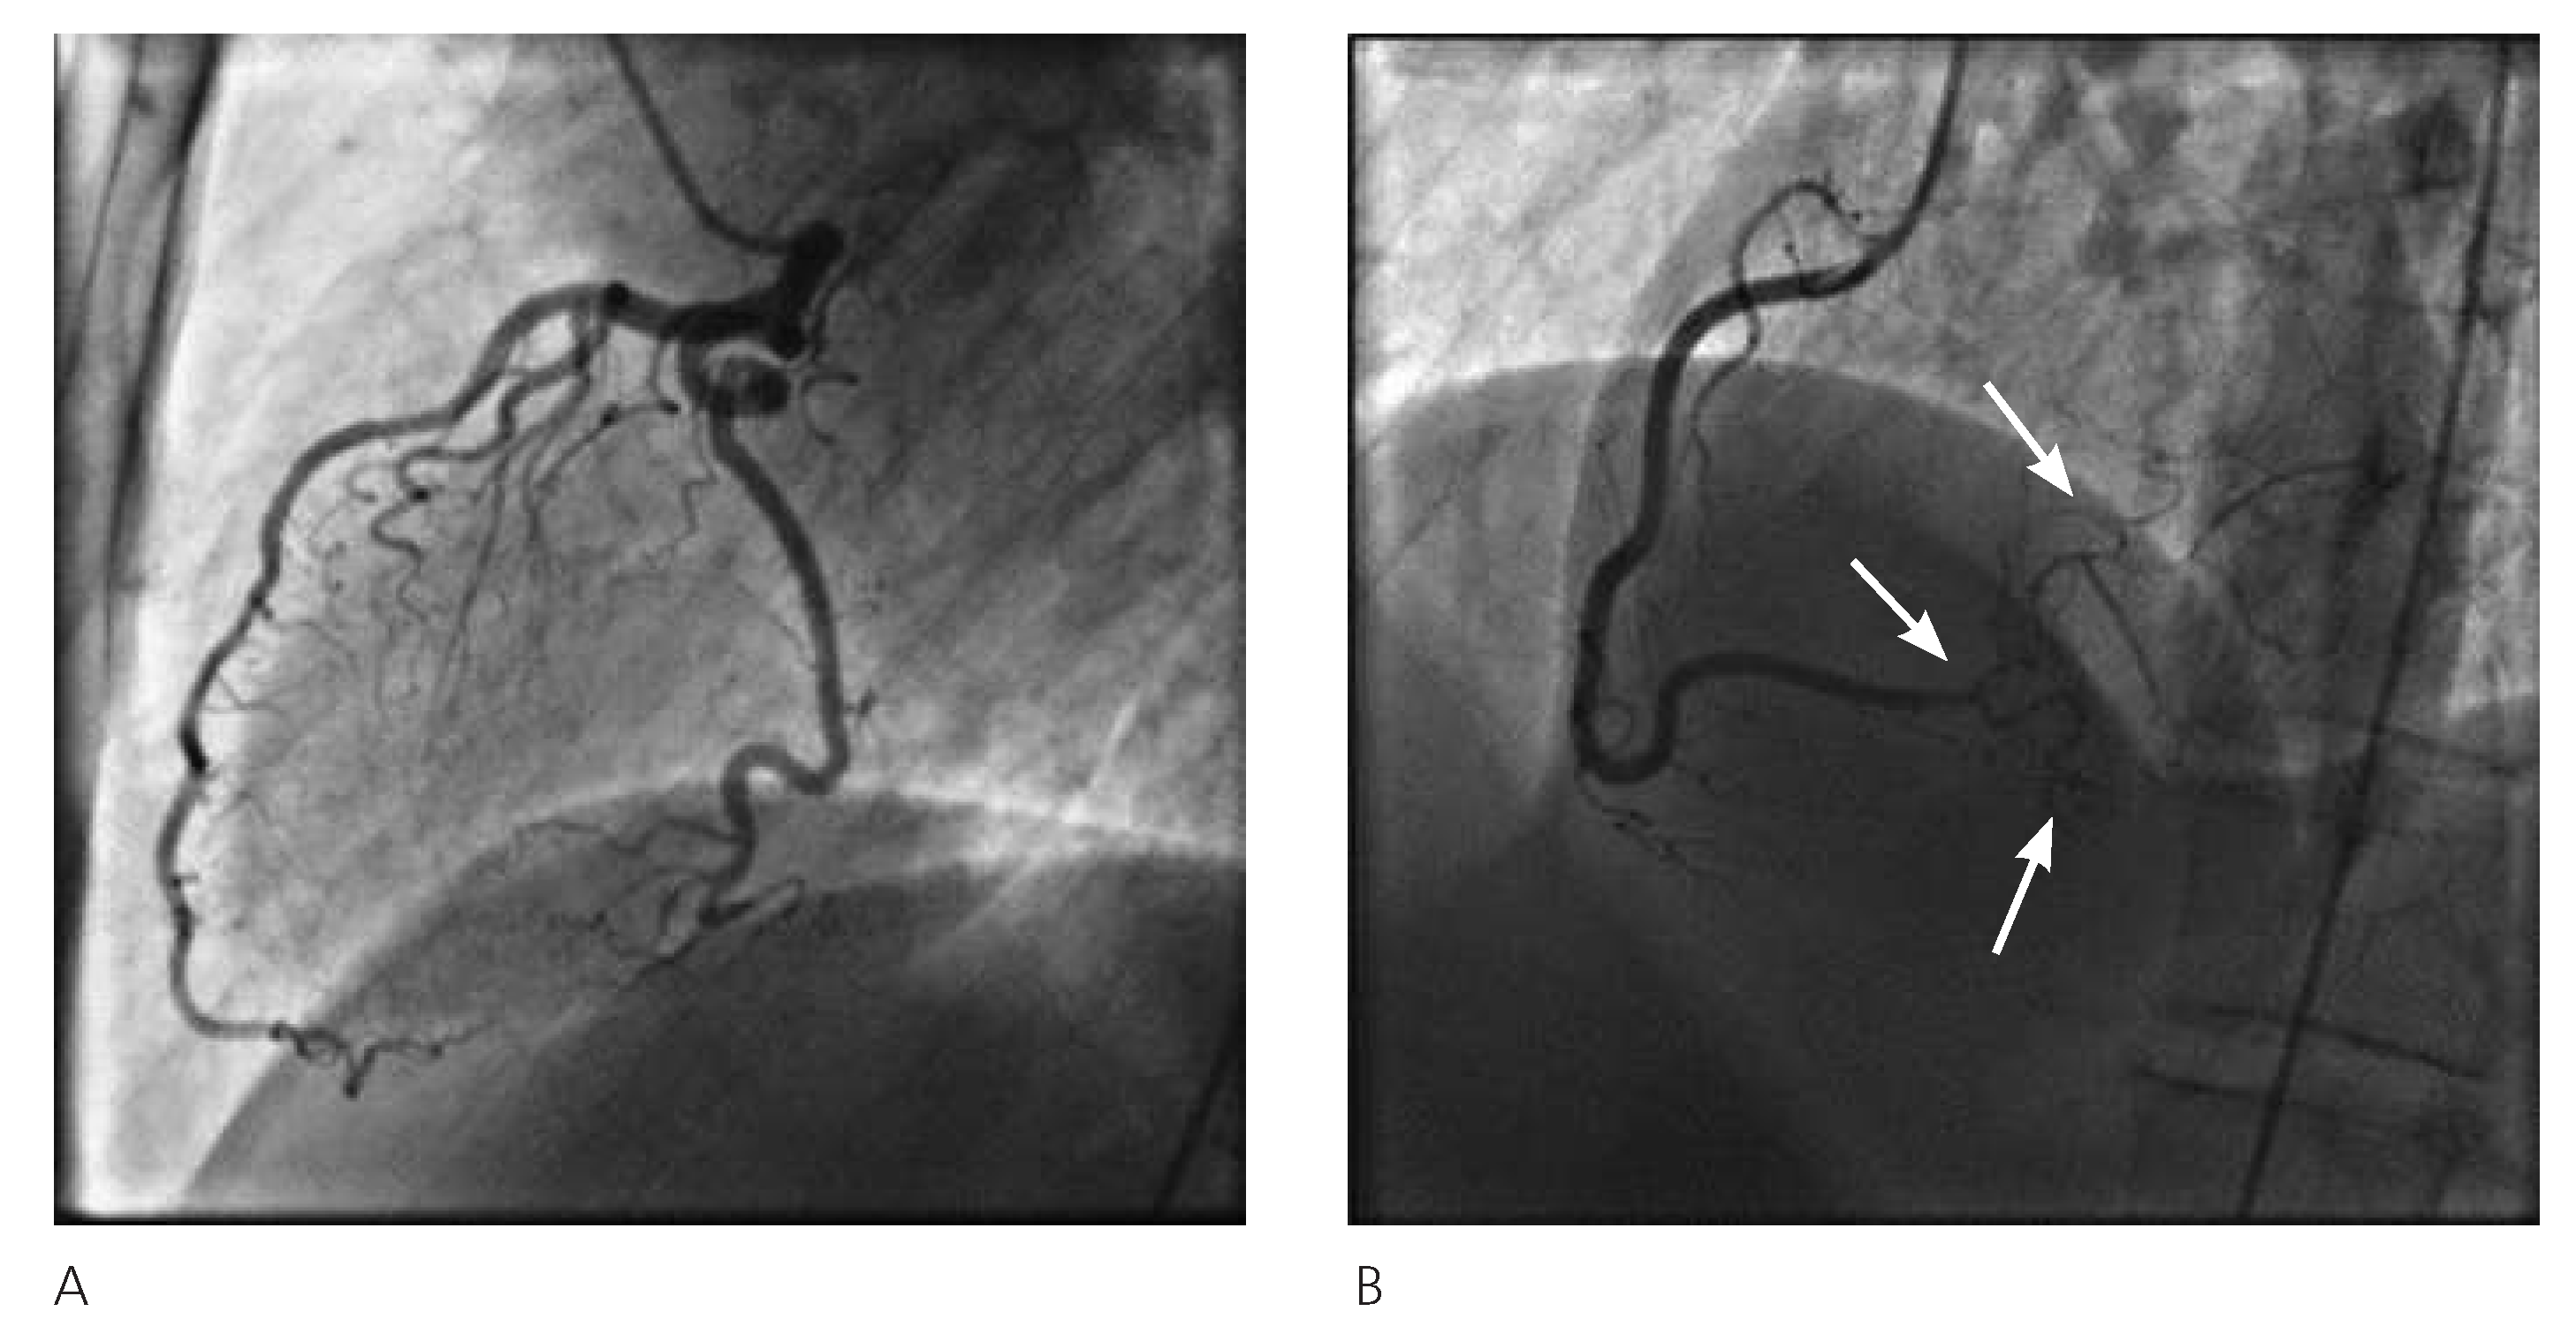

In November 2003, a 46-year-old woman, active smoker, with mild hypertension and a family history of cardiovascular disease, reported a sudden onset of pressurelike substernal chest pain, radiating to both arms: while being transported to the emergency department by ambulance, a cardiac arrest occurred with ventricular fibrillation as the first rhythm established. Cardiopulmonary resuscitation and direct current shock were performed and the return of spontaneous circulation was achieved. In the emergency department ECG showed regular sinus rhythm, 65 bpm, and ST depression in V2–V6 leads. The coronary angiography showed a long (around 25 mm) subtotal stenosis and narrowed vessel aspect (TIMI I) in the middle part of the tortuous LCx, with a small radiolucent defect in the proximal segment of the lesion, suggestive features of spontaneous dissection, without any other detectable coronary lesion. The patient underwent percutaneous coronary intervention (PCI) and three drug-eluting stents (Taxus-paclitaxel) were successfully implanted (Figure 1), resulting in restoration of TIMI III flow and resolution of symptoms. The patient improved and was discharged on double antiplatelet therapy for twelve months (Aspirin® and clopidogrel), beta-blocker and statin. Follow-up coronary angiography at three months demonstrated patency of the stents, without evidence of residual disease, and her medical treatment was confirmed. Thirty-four months later, in August 2006, the patient was admitted with unstable angina, positive troponin and T-wave inversion in precordial leads (V2–V5). The coronary angiography showed a fresh and long (>20 mm) dissection of the distal RCA propagating to the posterior lateral branch without any sign of disease in the other vessels (Figure 2). Once again the proximal segment of the lesion presented a tiny radiolucent line. In light of the unfavourable location of the lesion, its extension, the small size of the target vessel, and the symptoms easily managed with nitrates, a conservative treatment was deemed necessary. The patient had a favourable clinical course and discharge occurred three days later, on aspirin and clopidogrel for 3 months, beta-blocker and statin. In the follow-up the patient remained almost asymptomatic. Forty-eight months later, in Au gust 2010, because of recurrence of chest pain and inconclusive Echo-stress test, a new coronary angio graphy was performed. It showed a spontaneous recanalisation of the previously dissected RCA and posterior lateral branch, with a small persisting lesion (Figure 3); no sign of injury was found in the other vessels. Aspirin was confirmed at discharge. Since then, the patient is still on aspirin and beta-blocker, and completely asymptomatic at the follow-ups, last one performed in February 2014.

Figure 1. November 2003 coronary angiography. A Fresh, long dissection on middle LCx artery (arrows). Normal LAD artery. B Middle LCx artery PCI and stent implantation (arrows). C Normal RCA. LAD = left anterior descending artery; LCx = left circumflex artery; RCA = right coronary artery; PCI = percutaneous coronary intervention.